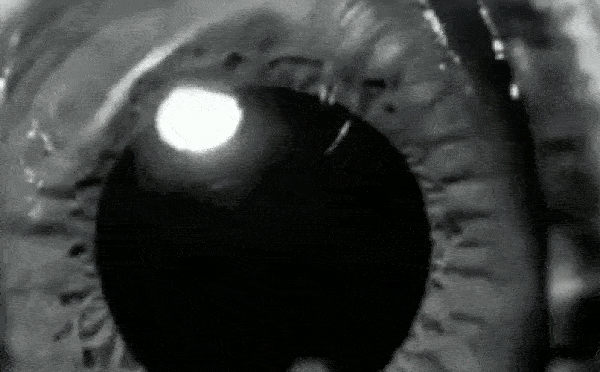

Sự giãn nở và co lại của đồng tử là những quá trình hoàn toàn tự động. Do nhiều yếu tố khác nhau kích hoạt. Ví dụ như bước vào môi trường sáng hoặc tối, nhưng một nghiên cứu điển hình gần đây cho thấy không phải lúc nào cũng vậy.

Một sinh viên trẻ ở Đức có thể tự điều khiển các cơ nhỏ bé điều chỉnh kích thước của đồng tử, một kỳ tích mà trước đây các nhà khoa học cho là không thể xảy ra.

Các nhà nghiên cứu chỉ ra rằng một số người có thể thay đổi kích thước đồng tử của họ thông qua "phương pháp gián tiếp", tuy nhiên, người đàn ông trẻ này có thể điều khiển trực tiếp cơ vòng trong mắt để điều chỉnh kích thước của đồng tử.

Người đàn ông Đức mà trong nghiên cứu tạm gọi là DW, nhận ra rằng anh ta có khả năng tự kiểm soát kích thước đồng tử của mình khi 16 tuổi. Điều này xảy ra khi anh cố gắng "thư giãn" nhãn cầu của mình sau một thời gian dài chơi game trên máy tính. Người bạn của anh nhận thấy rằng một trong những đồng tử của anh lớn hơn đáng kể so với đồng tử còn lại. Kể từ đó DW đã mài giũa siêu năng lực bất thường của mình.

“Tôi đã cho một người bạn thấy rằng tôi có thể điều chỉnh kích thước nhãn cầu của mình. Anh ấy nhận thấy rằng đồng tử của tôi trở nên nhỏ lại," DW chia sẻ với Christoph Strauch, tác giả của nghiên cứu, trợ lý giáo sư trong khoa tâm lý thực nghiệm tại Đại học Utrecht, Hà Lan.

Một số ít người có khả năng điều chỉnh sức mạnh của đồng tử bằng cách gián tiếp như suy nghĩ về ánh sáng chói lọi rồi bóng tối cực độ, hay bằng cách nhẩm tính điều gì đó. Các nhà nghiên cứu tại Đại học Ulm đã thử nghiệm DW để xem liệu anh ấy có đang sử dụng kỹ thuật nào đó, hay dựa vào nỗ lực trí óc hay không. Kết quả là anh ấy không dùng.

Trong suốt giai đoạn thử nghiệm, các nhà nghiên cứu không tìm thấy dấu hiệu nào cho thấy DW đang điều chỉnh kích thước đồng tử một cách gián tiếp. Bằng cách kiểm soát trực tiếp cơ mắt của mình, người đàn ông này có thể giãn đồng tử có đường kính lên tới 2,4 mm và thu hẹp chúng xuống 0,88 mm.

Chàng trai trẻ thậm chí còn có thể co đồng tử của mình vượt quá mức tối đa thường quan sát được khi tập trung vào các vật thể gần. Anh ấy nhìn rõ các vật thể gần khuôn mặt hơn gần hai lần so với khả năng bình thường khi không cần kiểm soát đồng tử.

Các nhà khoa học lưu ý rằng DW có thể kiểm soát kích thước đồng tử của mình trong khi thoải mái và trò chuyện với các nhà nghiên cứu.

Sau nghiên cứu, DW trở thành người đầu tiên trên thế giới được biết đến với khả năng tự kiểm soát kích thước đồng tử của mình. Strauch và các đồng nghiệp của ông tin rằng trong tương lai có nhiều người có khả năng bất thường sẽ liên hệ với nhóm, giúp họ hiểu rõ hơn về quá trình này.